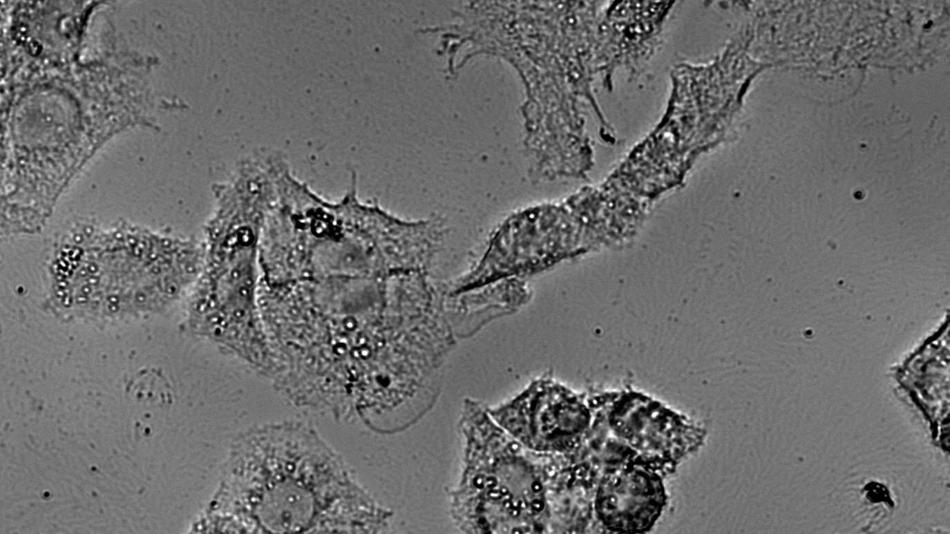

Experiment / VorführungLaserblick in die Zelle – Science oder Fiction?NeuThema: Digitalisierung NaturwissenschaftenZellen reagieren auf äußere Einflüsse, doch ihre Veränderungen sind für uns nicht direkt sichtbar. Die Kombination aus Mikroskopie, winzigen Goldpartikeln und Laserstrahlen gemeinsam mit modernster digitaler Datenverarbeitung ermöglicht es, vielfältige Informationen von Zellen mit der Raman-Spektroskopie zu erhalten. Zum Beispiel, wie sich eine Krebszelle verändert, wenn sie mit Medikamenten behandelt wird.FH Wiener Neustadt17:00 - 23:00